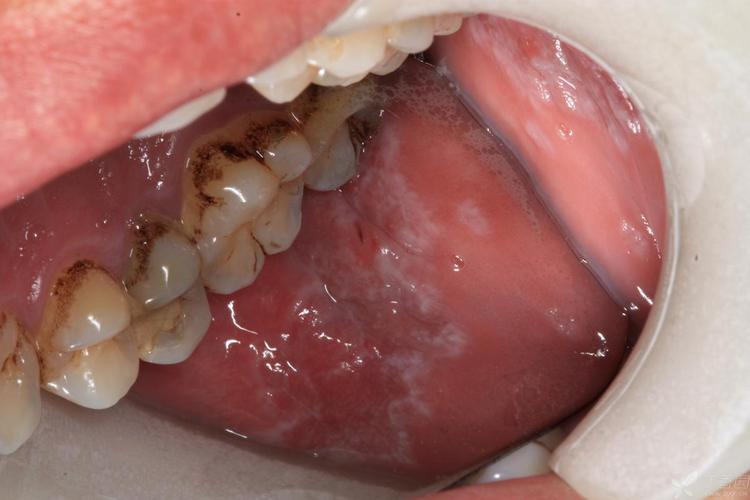

口腔扁平苔藓早期症状图片长啥样?

口腔扁平苔藓早期症状图片大全:一张图教你自我识别,早发现早安心! ** 别把口腔“网纹”当溃疡!医生教你3招识别扁平苔藓,避免误诊误治(图片来源网络,侵删) 引言:您是否发现口腔里出现了“不明图案”? “医生,我嘴里最近长了一些白白的东西,像花纹一样,不疼不痒,是上火了吗?还是缺乏维生素?” 在口腔...